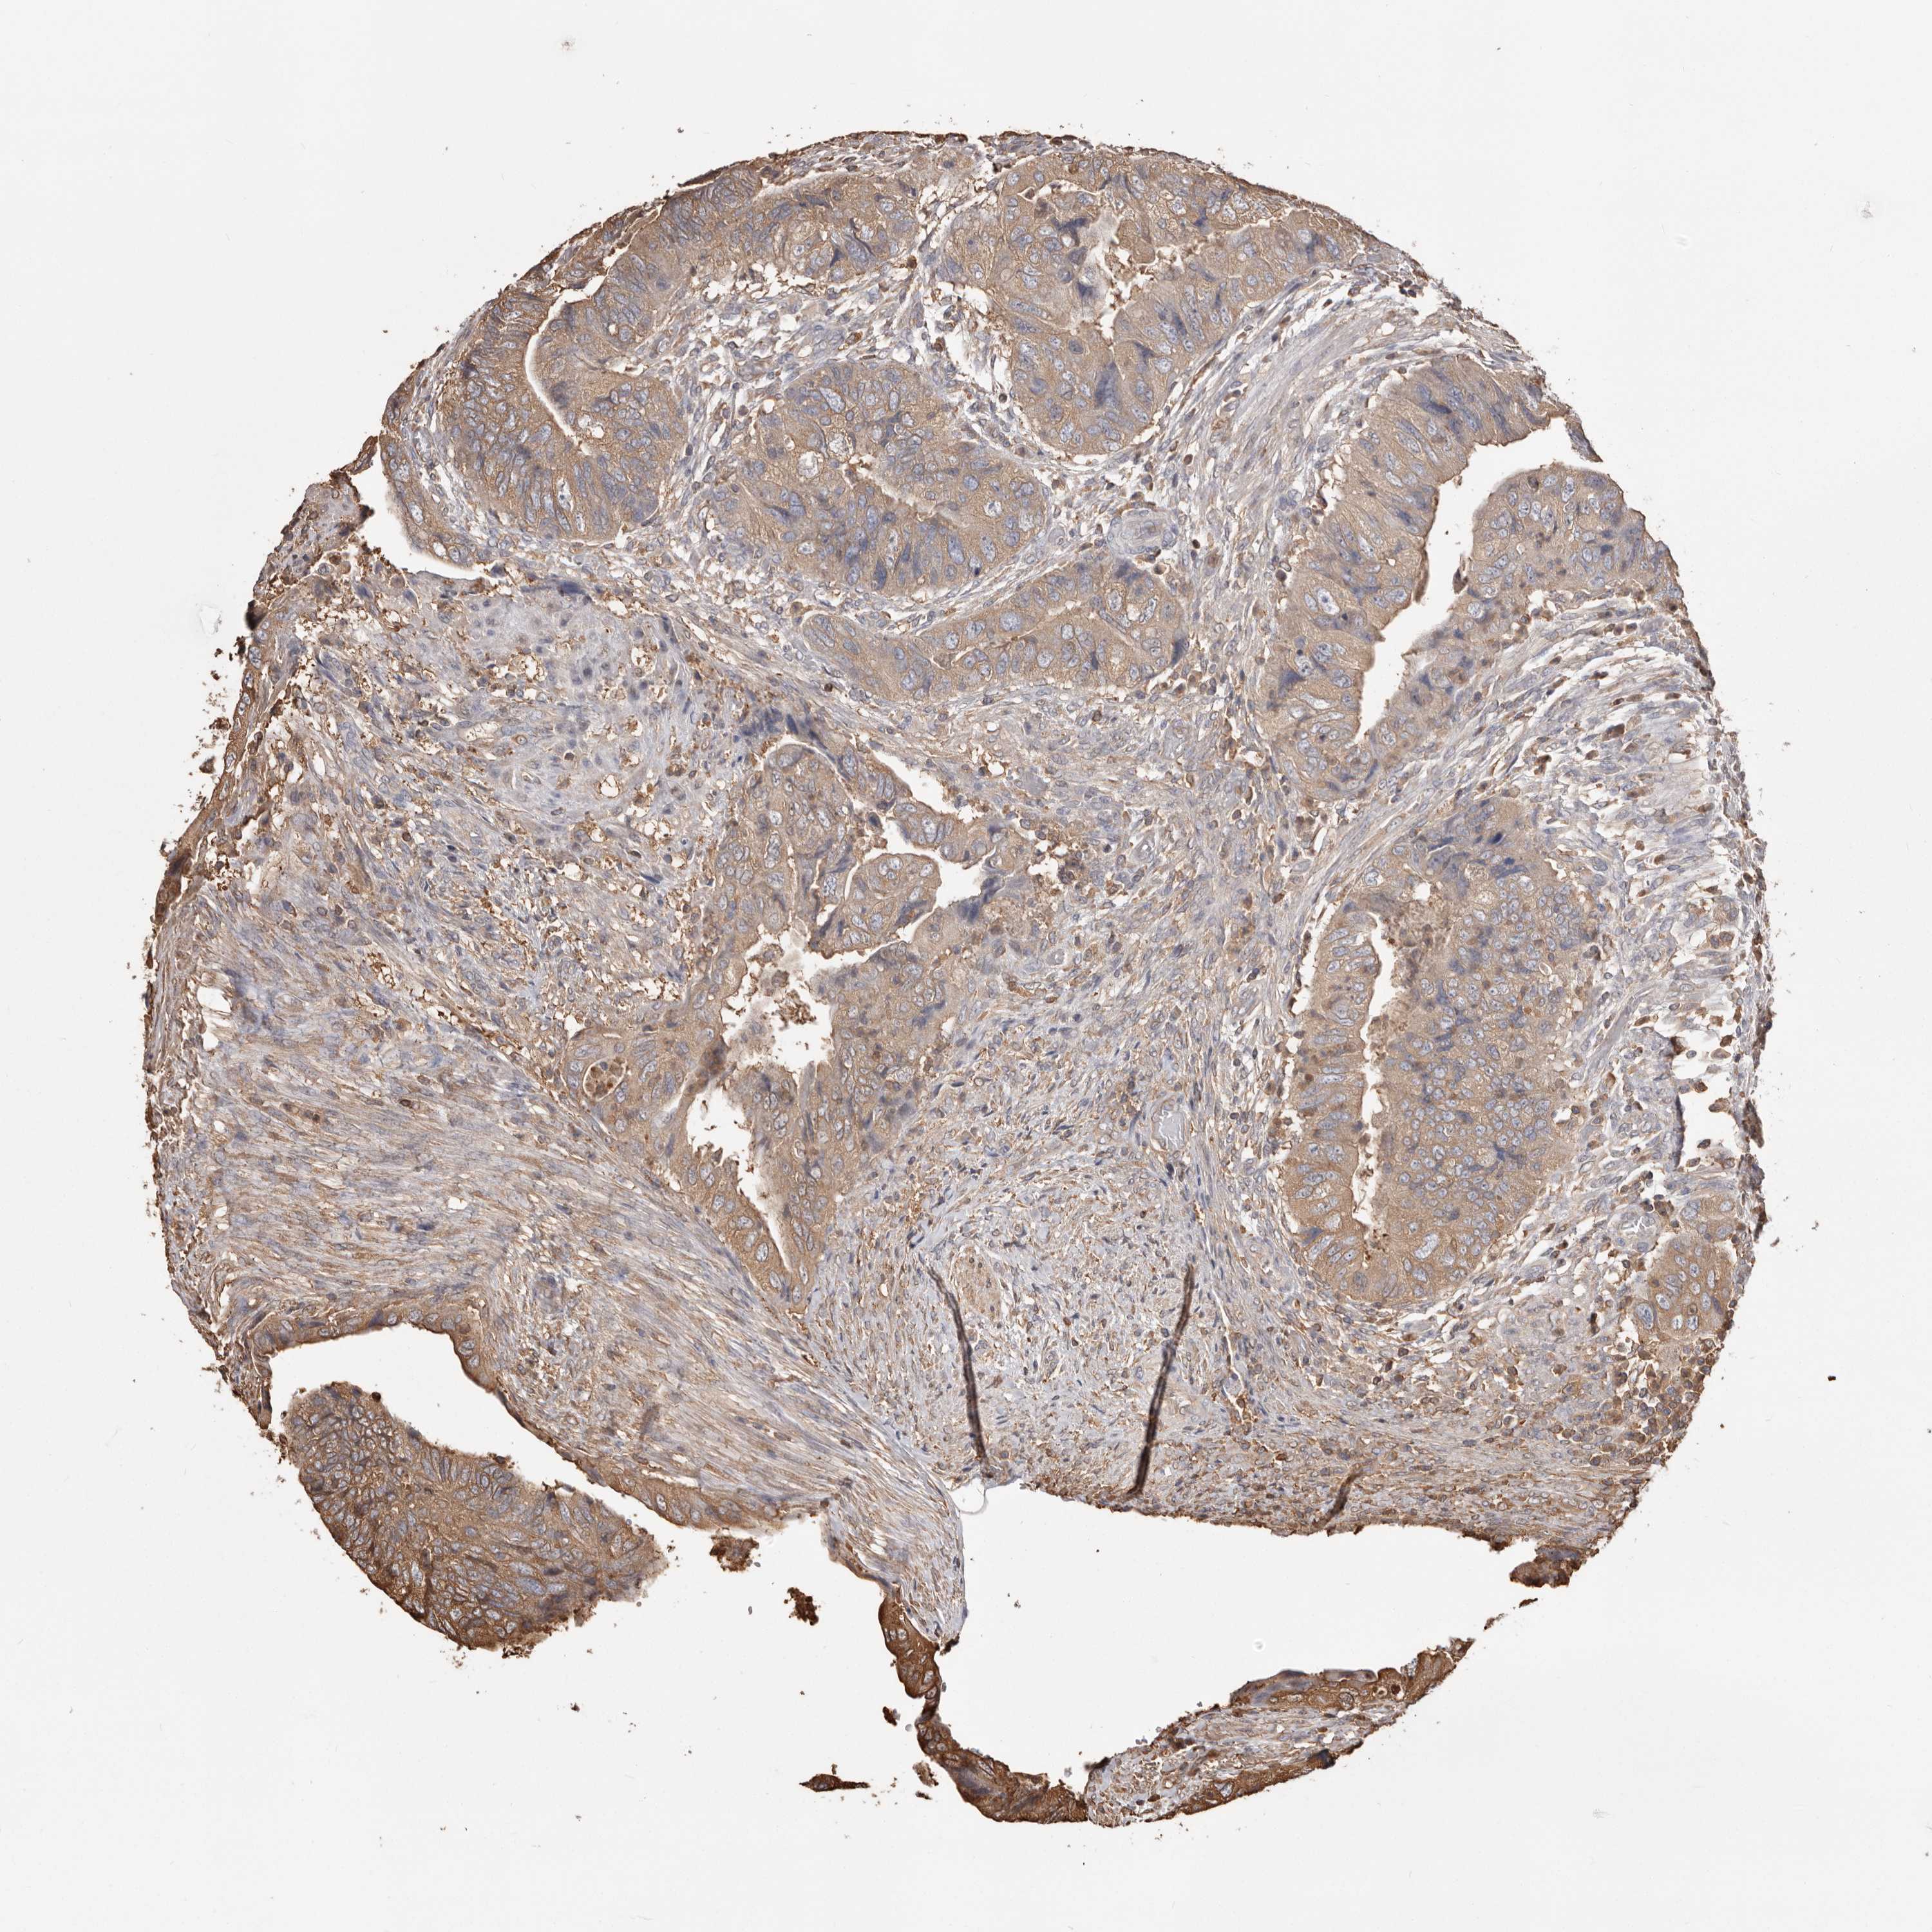

CANCER COLORECTAL CANCER Show tissue menu

Colorectal cancer

Human cancer

Colon adenocarcinoma